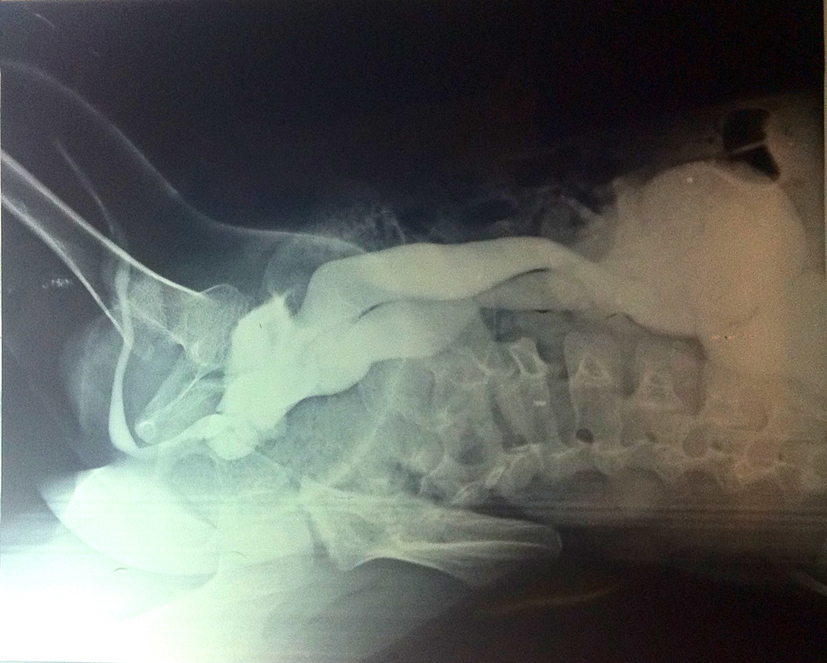

A 7-year-old boy presented with dull pain in right flank with repeated episodes of urinary tract infection. Clinically, no abnormality was detected. Ultrasonography revealed right gross hydronephrosis with hydroureter up to ureterovesical junction. Micturating cystourethrogram suggested grade V reflux in both ureters of complete duplication (Fig. 1). Right kidney had 20% split function (glomerular filtration rate: 18 mL/min). Cystoscopy revealed both the ureteric orifice in small prostatic urethral diverticulum (Fig. 2). Common sheath ureteric reimplantation was done by Politano-Leadbetter technique with double J stenting (Fig. 3, 4).

![]() Click for large image | Figure 1. Micturating cystourethrogram. |